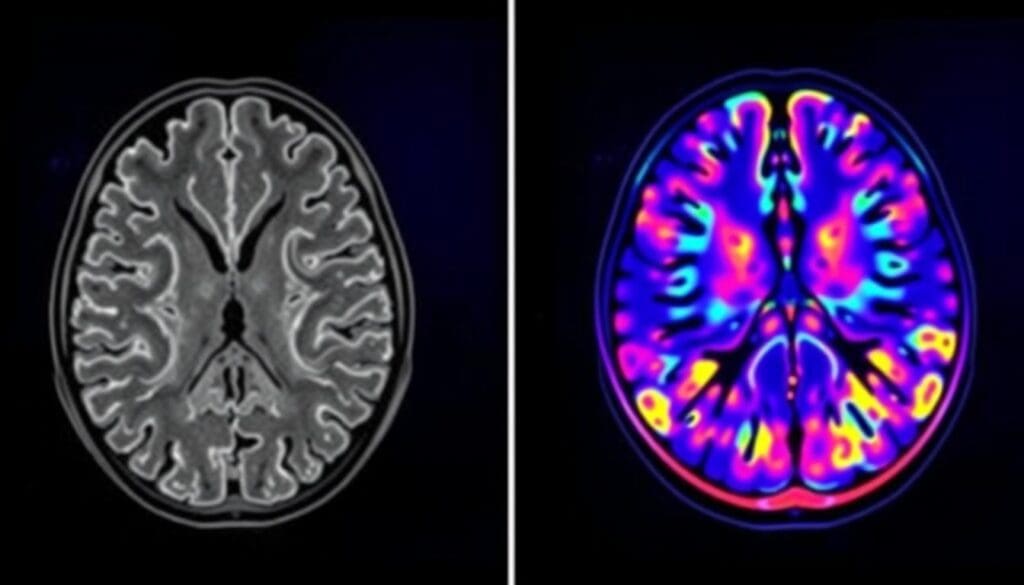

Structural vs Functional Imaging

MRI shows detailed pictures of body parts and tissues. It helps find problems with how things are put together. PET scans, on the other hand, show how body parts work. They are great for seeing how active tissues are and finding diseases like cancer.

In short, MRI is good for seeing the body’s layout. PET scans are better for seeing how the body functions.

Resolution and Detail Capabilities

MRI is better at showing detailed images of soft tissues. This is why it’s great for looking at the brain and muscles. PET scans, while not as detailed in anatomy, are excellent at spotting changes in how tissues work. This is very important for finding cancer and seeing how it spreads.